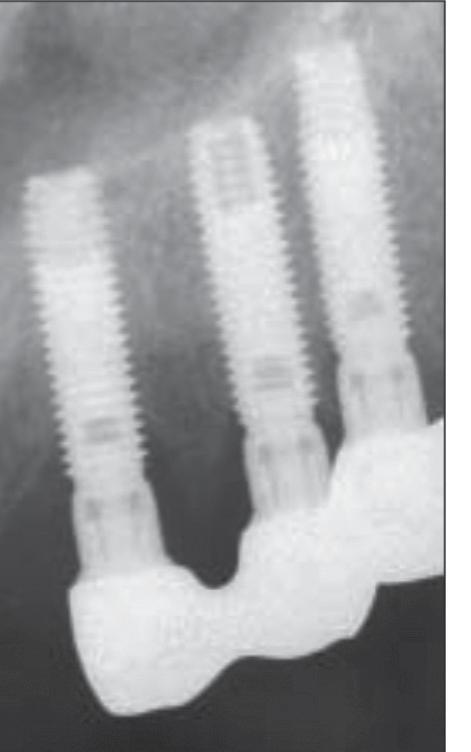

a D-B root amputation. It served temporarily as a distal abutment for the partial prosthesis following restoration of the occlusal vertical dimension. The patient was advised of the necessity of implant therapy for a more stable rehabilitation of the maxillary right quadrant. Three 16-mm-long machined-surface Screw-Vent implants (CoreVent System, Encino, CA) were placed to replace the maxillary right premolars and first molar. In November 1991, the abutments were connected, and an implant-supported fixed partial prosthesis with a distal cantilever was placed. The patient was seen every 6 months for maintenance. Periapical radiographs were obtained annually of the patient’s right side (Figs 1 and 2).

Fig 1 - Peri-implant bone level 1 year post-loading. Minimal bone loss on the intermediate implant. Stability of the bone level on the 2 adjacent implants, which were placed in the maxillary right first premolar and first molar sites.

Fig 2 - Bone level 5 years postloading. Stability of the periimplant bone level can be observed

The peri-implant bone level was found to be stable at the level of the first thread after 9 years of loading (Fig 3).

Prosthetic failure of the maxillary left premolars and first molar occurred in October 1999. The fixed partial prosthesis became loose due to recurrent decay and poor crown-to-root ratio. It was decided to extract the remaining teeth and convert to an implant-supported fixed restoration. Three Brånemark implants (Nobel Biocare, Göteborg, Sweden) were placed in the maxillary left quadrant, and the patient was referred to her dentist for the placement of a temporary removable prosthesis to restore esthetics and function while implant osseointegration was achieved. The dentist removed the maxillary right implant-supported partial prosthesis and placed an overdenture. The patient was seen in May 2000 for abutment connection on the maxillary left implants. Periapical radiographs were obtained to assess the osseointegration. Severe bone loss was observed on the implants in the maxillary right first premolar site and the maxillary right first molar site (Figs 4 to 6).